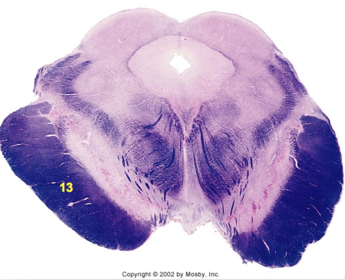

| Hypoglossal nucleus | |

| Hypoglossal nerve | |

| Dorsal motor nucleus of X | |

| Nucleus ambiguus | |

| Solitary tract | |

| Solitary nucleus | |

| ALS | |

| Medial lemniscus | |

| Medial longitudinal fasciculus | |

| Spinal tract of V | |

| Spinal nucleus of V | |

| Lateral (external, accessory) cuneate nucleus | |

| Medullary pyramids | |

| Anterior spinocerebellar tract | |

| CN IX | |

| Inferior cerebellar peduncle | |

| Inferior olivary complex | |

| Dorsal cochlear nucleus | |

| Inferior vestibular nucleus | |

| Medial vestibular nucleus | |